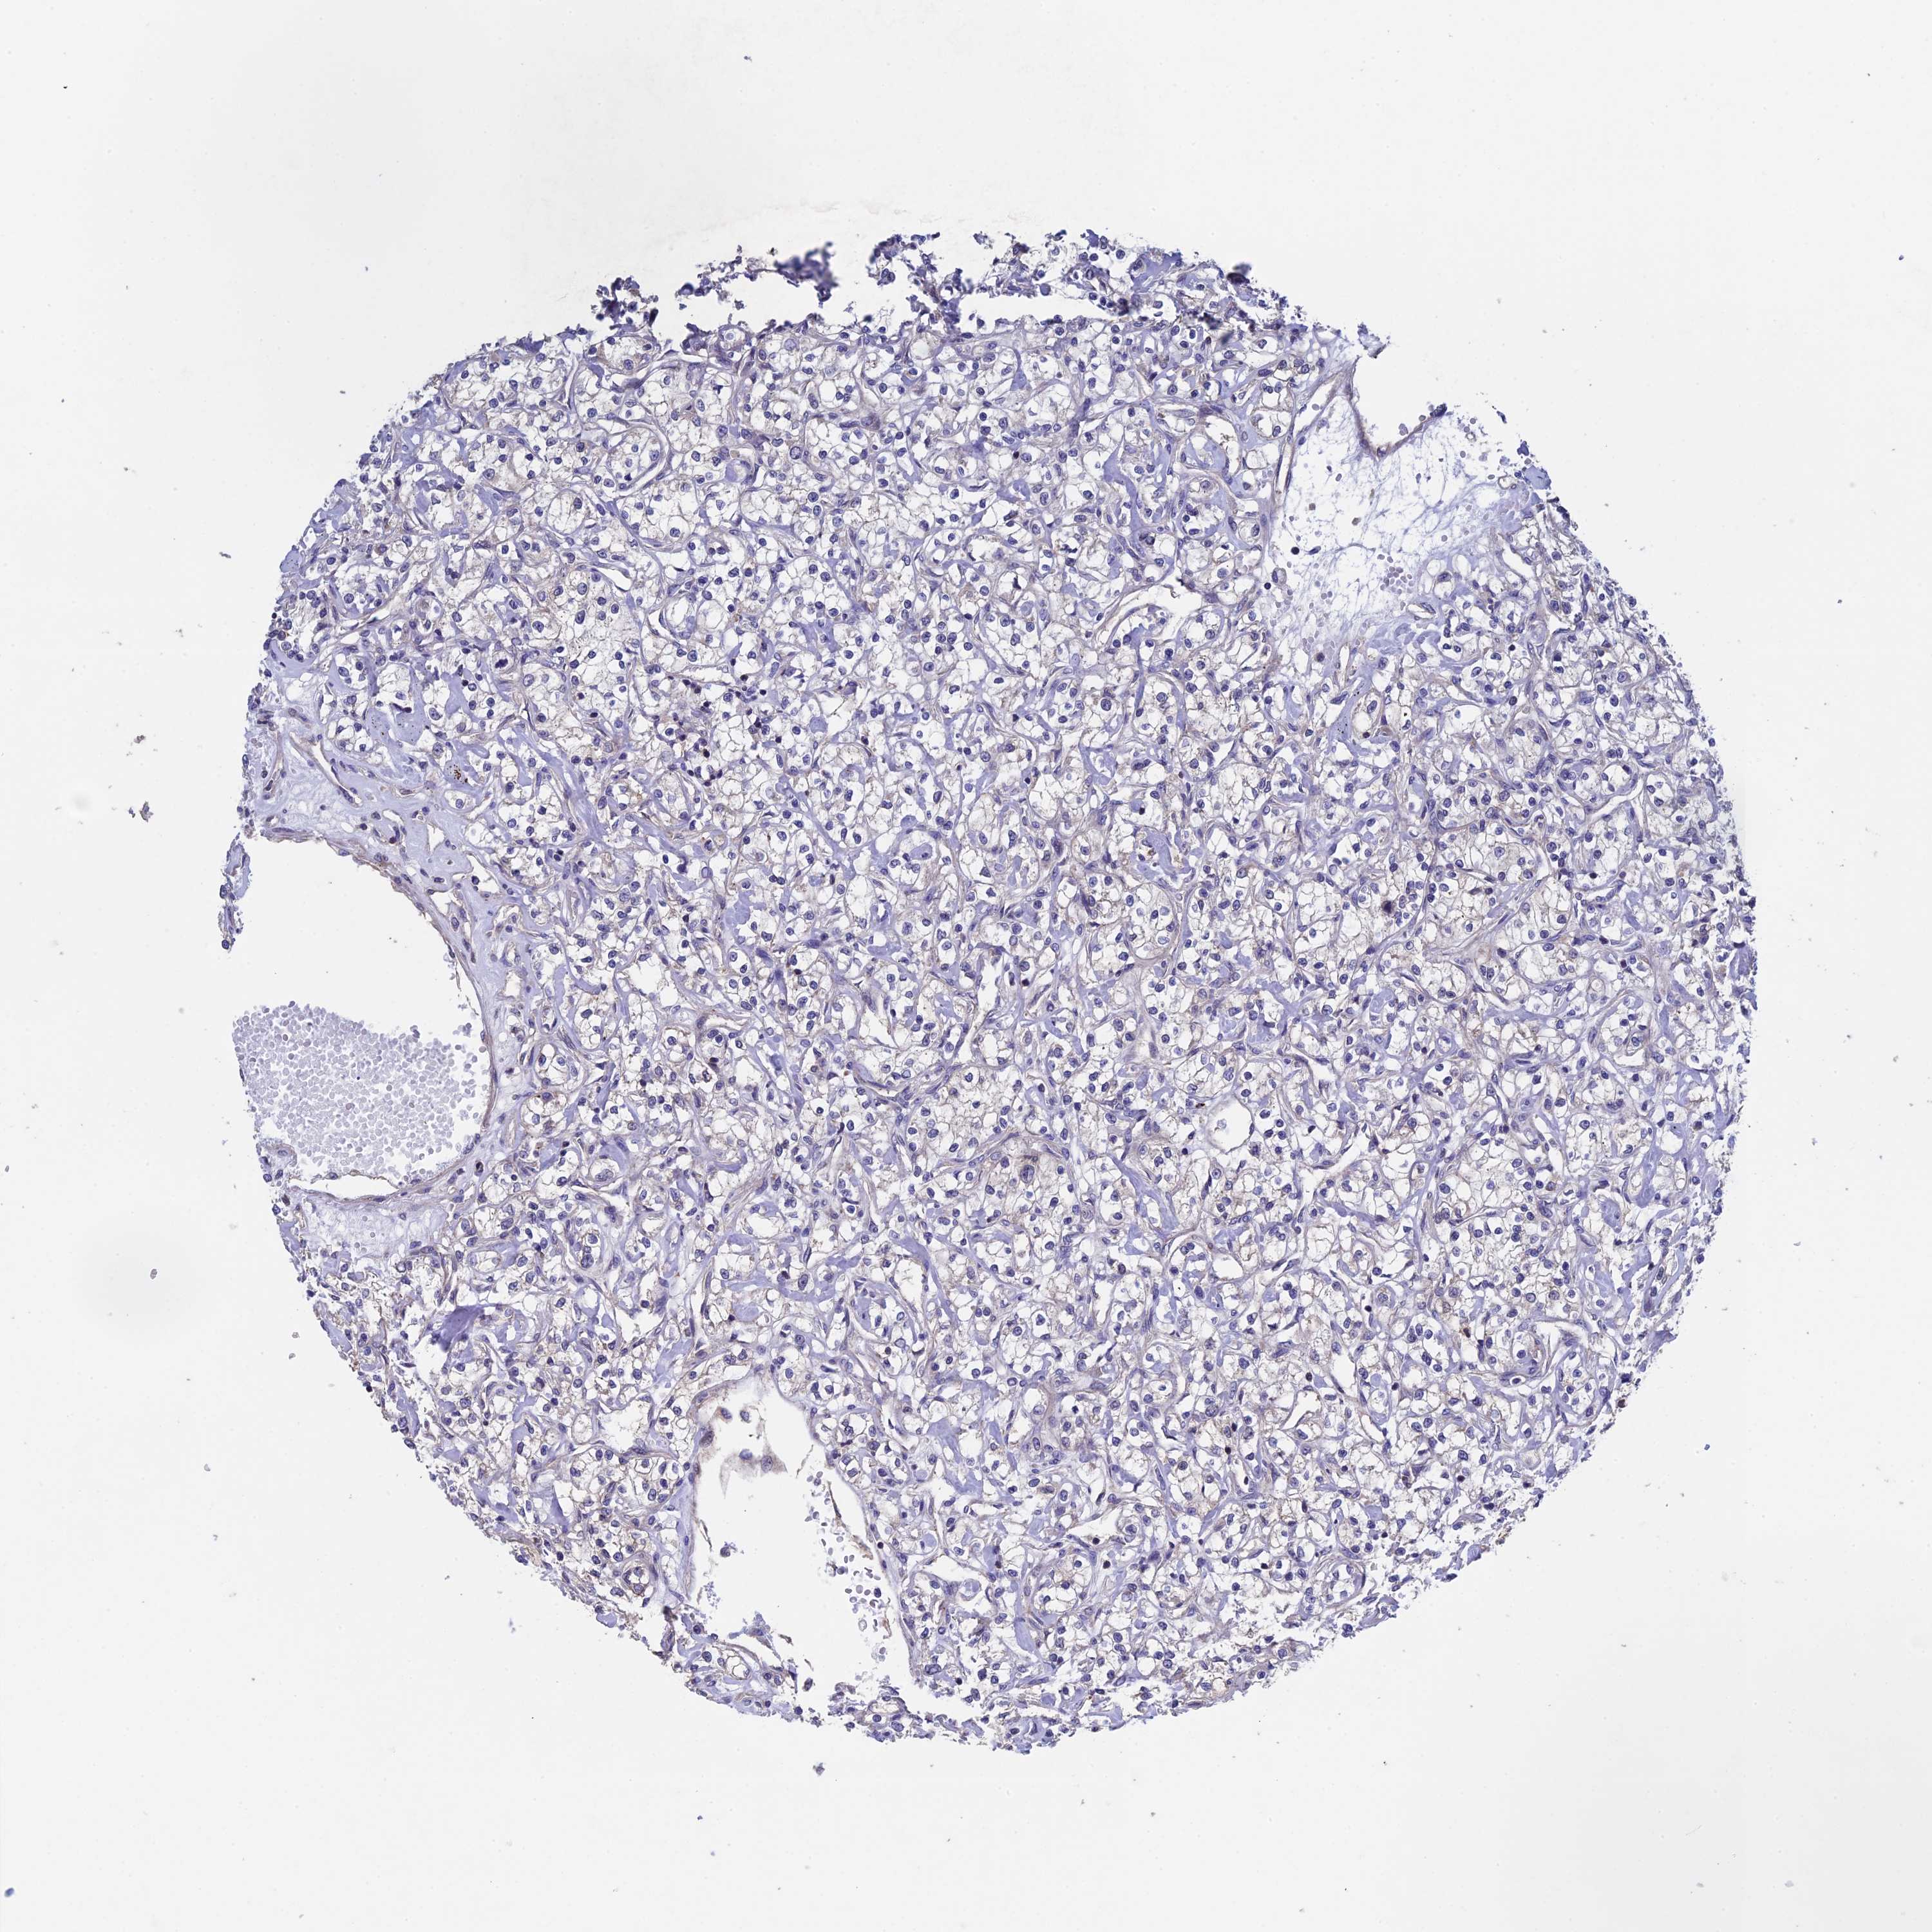

KIDNEY RENAL PAPILLARY CELL CARCINOMA (TCGA) - Interactive survival scatter ploti

The Survival Scatter plot shows the clinical status (i.e. dead or alive) for all individuals in the patient cohort, based on the same data that underlies the corresponding Kaplan-Meier plots. Patients that are alive at last time for follow-up are shown in blue and patients who have died during the study are shown in red.

The x-axis shows the expression levels (FPKM) of the investigated gene in the tumor tissue at the time of diagnosis. The y-axis shows the follow-up time after diagnosis (years). Both axes are complimented with kernel density curves demonstrating the data density over the axes. The top density plot shows the expression levels (FPKM) distribution among dead (red) and alive patients (blue). The right density plot shows the data density of the survived years of dead patients with high and low expression levels respectively, stratified using the cutoff indicated by the vertical dashed line through the Survival Scatter plot. This cutoff is automatically defined based on the FPKM cutoff that minimizes the p-score. The cutoff can be changed by dragging the vertical line or by entering a cutoff value in the square labeled "Current cut-off".

Under the Survival Scatter plot the p-score landscape (black curve; left axis) is shown together with dead median separation (red curve; right axis). Dead median separation is the difference in median mRNA expression between patients who have died with high and low expression, respectively. It is calculated as follows: median FPKM expression of dead patients with high expression - median FPKM expression of dead patients with low expression. This is intended to aid the user in visually exploring custom cutoffs and the associated p-scores and dead median separation.

Individual patient data is displayed and can be filtered by clicking on one or more of the category buttons on the top of the page. Categories describing expression level and patient information include: high, low, alive, dead, female, male and tumor stages. The scale of the x-axis can be toggled between linear and log-scale by clicking on the "x log" button. Mouse-over function shows TCGA ID, patient information and mRNA expression (FPKM) for each patient.

& Survival analysisi

Kaplan-Meier plots summarize results from analysis of correlation between mRNA expression level and patient survival. Patients were divided based on level of expression into one of the two groups "low" (under cut off) or "high" (over cut off). X-axis shows time for survival (years) and y-axis shows the probability of survival, where 1.0 corresponds to 100 percent.

LCMT1 is not prognostic in Kidney Renal Papillary Cell Carcinoma (TCGA)